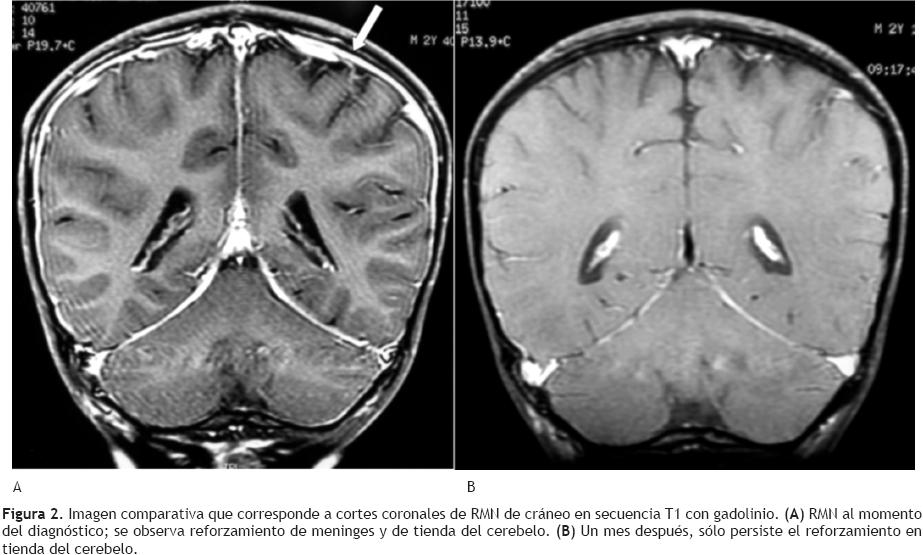

Infarto maligno de la arteria cerebral media en una ...

Infarto maligno de la arteria cerebral media en una ... from scielo.conicyt.cl